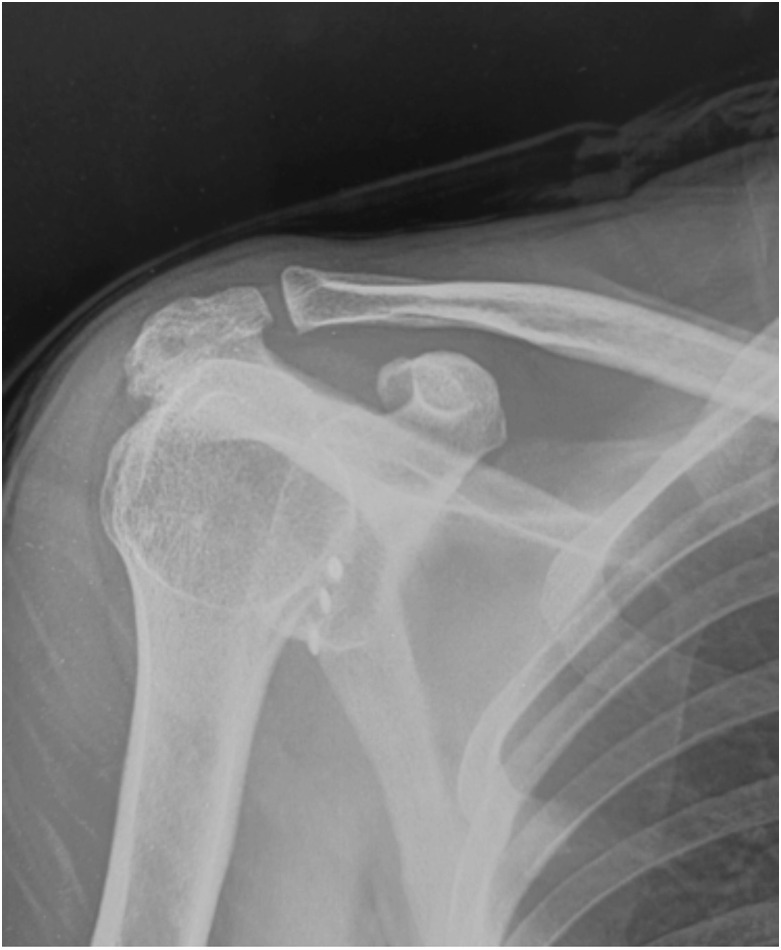

Abstract Image